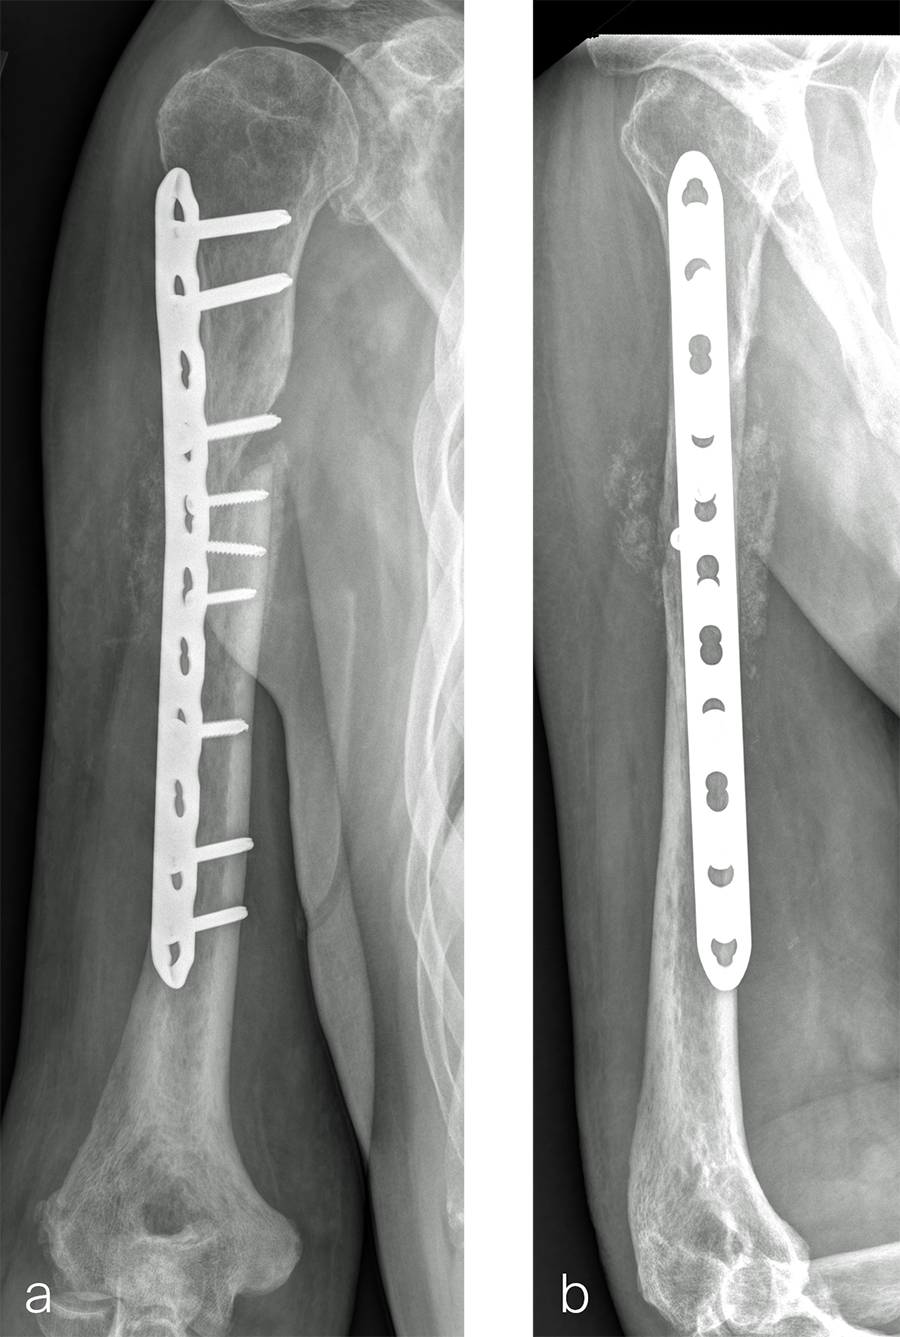

Case 2: RIA 2 use at the humerus (provided by Mark Lee, Sacramento, US)

The patient was an 83-year-old right-hand dominant man who sustained a closed right humeral shaft fracture approximately 10 months before presentation. He was not initially offered surgical care and was treated with functional bracing. The patient has moderate pain but mainly complains of instability and lack of strength in his right arm. He was offered surgical nonunion repair with autogenous iliac crest bone grafting but declined iliac crest harvest. X-rays showed oblique nonunion with resorption and confirmed diagnosis of pseudarthrosis (Fig 7).

After debridement and resection of the pseudarthrosis, we accessed the distal segment of the humeral canal and used a small caliber RIA 2 reamer head to harvest intramedullary bone graft (Fig 8) for final plate fixation (Fig 9).